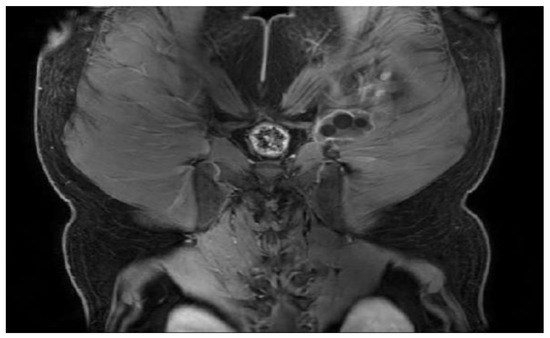

T2W MRI sequences, coronal—Hydatid cyst of left iliopsoas muscle and left thigh, with daughter cells and Serpent sign present [8] (part 1).

Figure 6.

T2W MRI sequences, coronal—Hydatid cyst of left iliopsoas muscle and left thigh, with daughter cells and Serpent sign present [8] (part 2).

Figure 7.

T2W MRI sequence, sagittal—Hydatid cyst left iliopsoas muscle and left thigh (part 1).